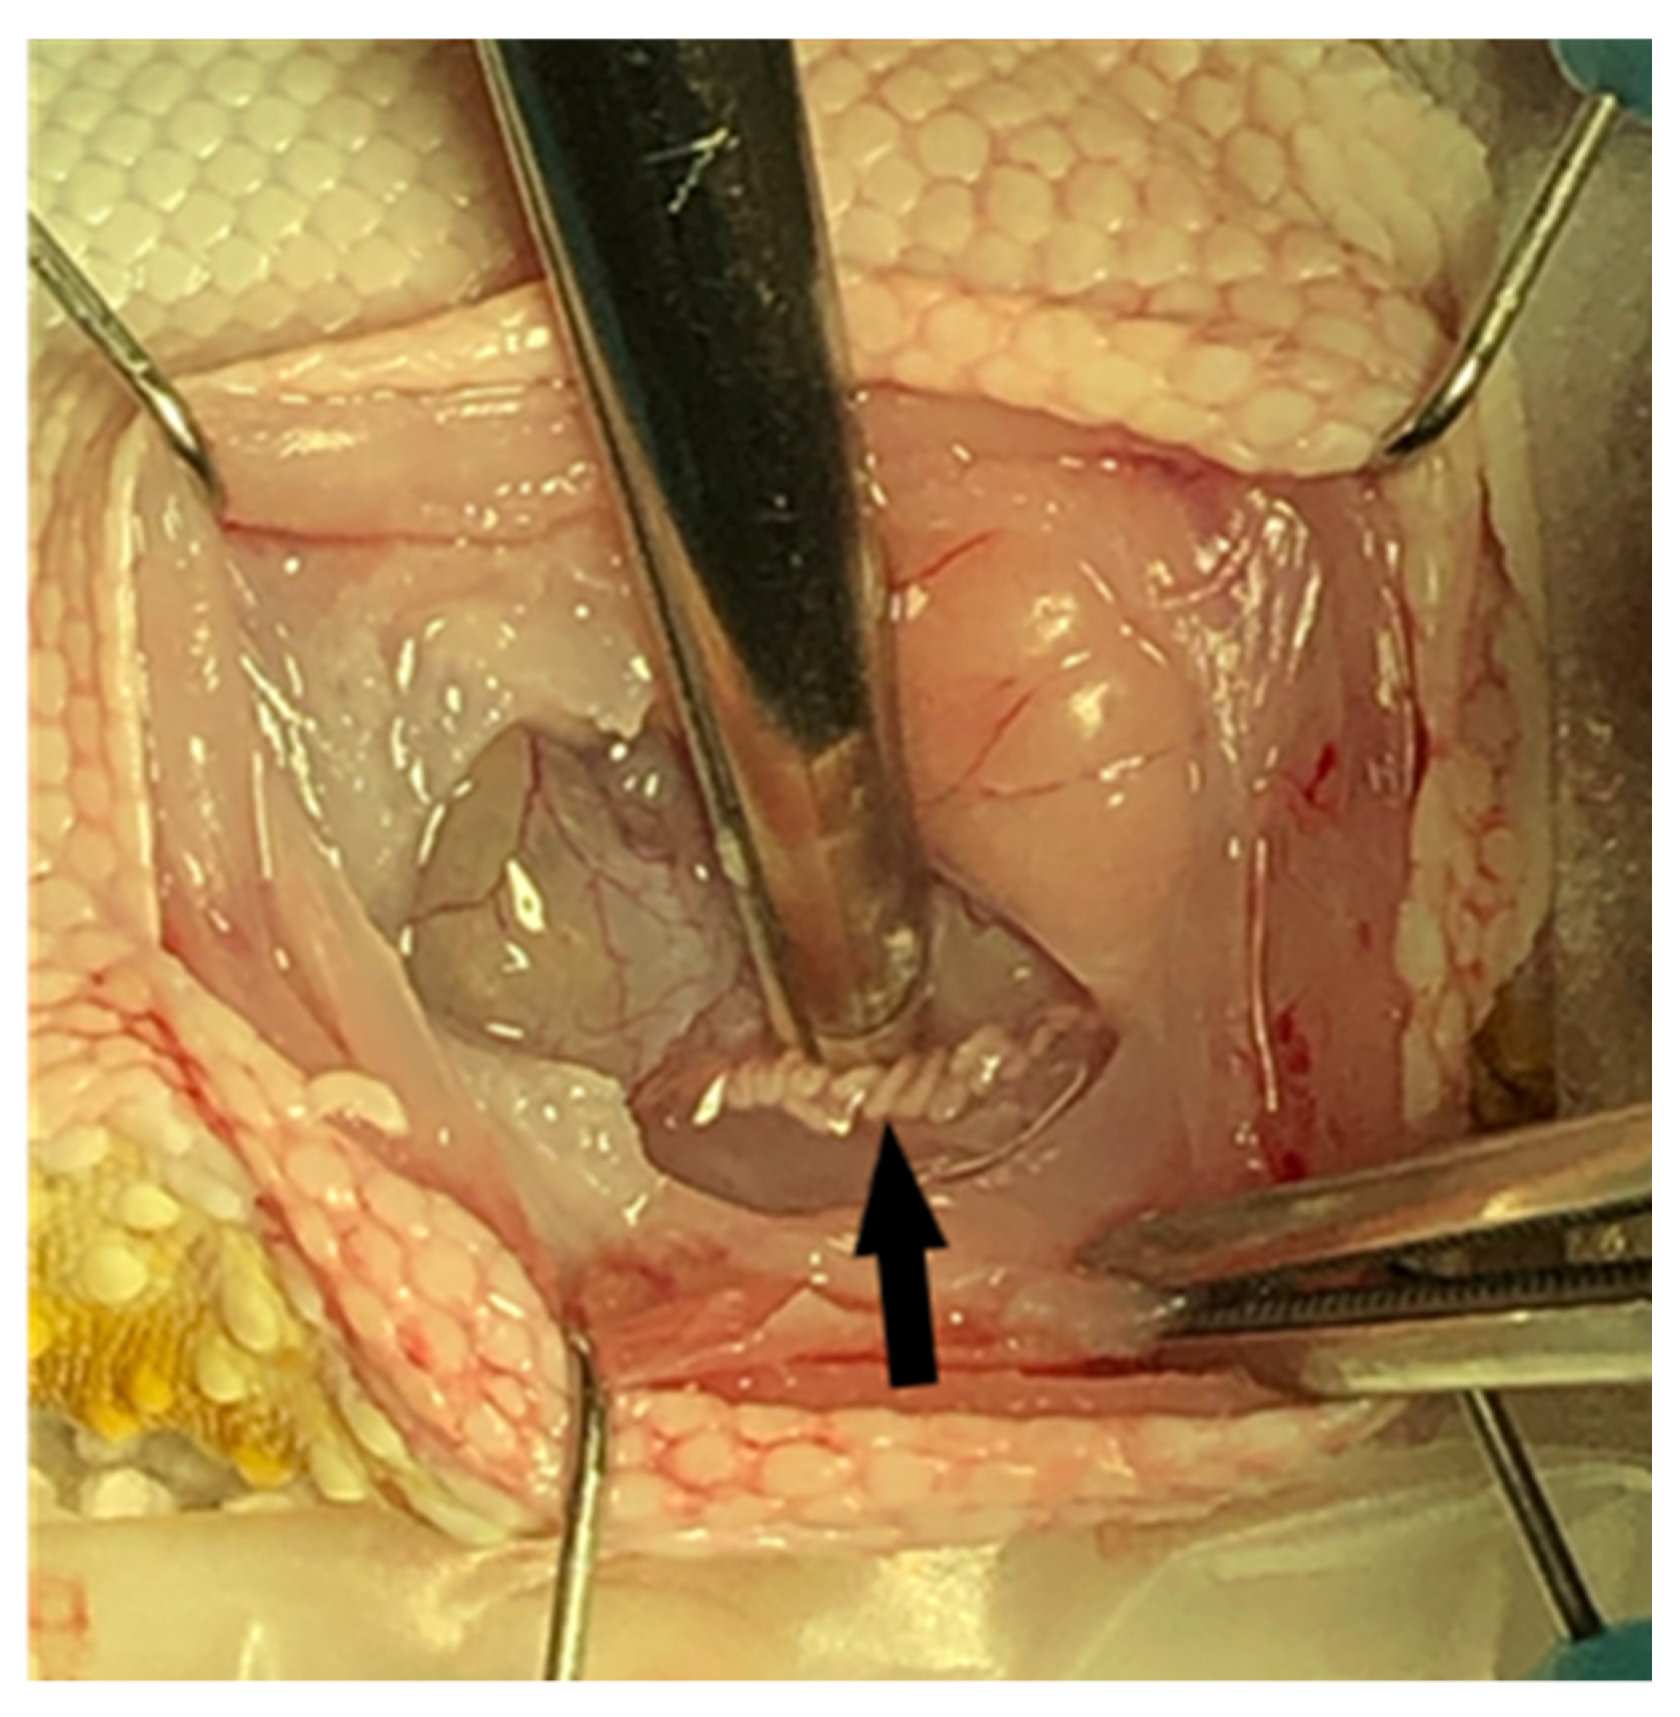

2.8. Unilateral Orchidectomy and Epididymectomy Procedures

On day 63 of the study, all twenty-four geckos underwent a surgical procedure to remove their right testicle and epididymis for morphometric measurements and gross and histopathological assessment. Each gecko was already anesthetized with isoflurane inhalant gas for venipuncture, ultrasound, and electrostimulation, and was administered subcutaneous injections of dexmedetomidine (Zoetis Services LLC, Parsippany, NJ, USA) 0.025 mg/kg, hydromorphone (Hospira, Inc., Lake Forest, IL, USA) 0.5 mg/kg, and meloxicam (OstiLox, VetOne, Boise, ID, USA) 0.3 mg/kg for additional sedation and analgesia just prior to surgery. Anesthesia was monitored throughout the procedure by measuring the respiratory rate, Doppler heart rate, and presence/absence of muscle tone and reflexes. The geckos were placed in dorsal recumbency, and their surgical site (ventral right abdominal region) was aseptically prepared with chlorohexidine scrub (VetOne, Boise, ID, USA) and 0.9% sterile saline. A #11 scalpel blade (Bard-Parker, Aspen Surgical Products, Inc., Caledonia, MI, USA) was used to make an initial paramedian incision on the right side of the abdomen, and Metzenbaum scissors were used to extend the body wall incision (3–4 cm). A Lone Star self-retaining retractor (Cooper Surgical Inc., Trumbull, CT, USA) was used to enhance visualization within the coelomic cavity. The ventral aspect of the intra-abdominal fat pad was immediately visualized upon entering the coelomic cavity. Gentle retraction of the fat pad revealed that the thin-walled urinary bladder was adhered to the dorsal wall of the fat pad. Medial displacement of the intestines using a cotton tipped applicator (Puritan Medical Products, Guilford, ME, USA) revealed the right testicle (Figure 3) and epididymis along the dorsal body wall (Figure 4). Once in the visual field, the thin mesorchium at the cranial pole of the testicle was gently grasped with atraumatic forceps to aid in the exteriorization and visualization of the testicle. A small hemoclip (Titanium ligating clips, Weck, Morrisville, NC, USA) was placed on the testicular artery and veins to control hemostasis, and the testicle was dissected from the remainder of the mesorchium for removal. The remaining epididymis was then grasped at its cranial end and traced caudally so an additional hemoclip could be placed and the epididymis removed. Unfortunately, it was challenging to remove the testicle and epididymis en bloc. Sterile cotton tip applicators were used to apply pressure for additional hemostasis as necessary, and the abdomen was flushed with sterile saline prior to closure. The body wall was closed with 4-0 Maxon (Coviden, Mansfield, MA, USA) in a continuous pattern, and the skin was also closed with 4-0 Maxon using a horizontal mattress pattern. Sterile skin glue (GLUture, Zoetis, Kalamazoo, MI, USA) was applied to the incision to reduce seepage. A subcutaneous injection of atipamezole (Zoetis Services LLC, Parsippany, NJ, USA) 0.5 mg/kg was administered to reverse the dexmedetomidine. The geckos were monitored post-operatively until all reflexes had returned and they were able to ambulate normally. Each animal received an additional injection of hydromorphone 0.5 mg/kg subcutaneously the following day, in addition to 0.3 mg/kg meloxicam subcutaneously once daily for three consecutive days to minimize discomfort. Animals were observed daily for 6 weeks, post-operatively, for any negative side effects associated with the surgical procedure, including anorexia, depression, discharge or swelling at the incision site, dehiscence, and lack of energy or ambulation.